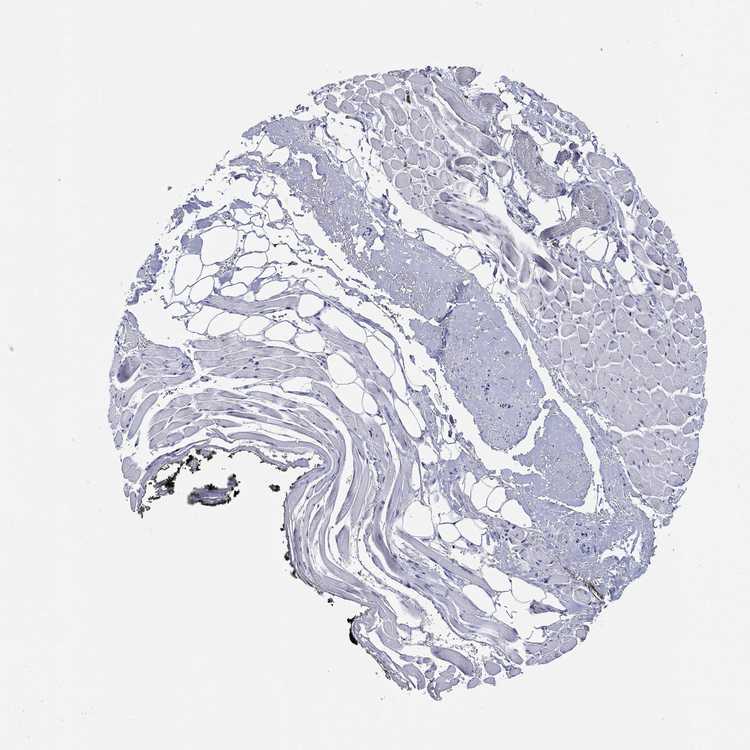

ADIPOSE TISSUE - Antibody stainingi

Antibody staining in the annotated cell types in the current human tissue is reported as not detected, low, medium, or high, based on conventional immunohistochemistry profiling in selected tissues. This score is based on the combination of the staining intensity and fraction of stained cells.

Each image is clickable and will lead to virtual microscopy that enables deeper exploration of all samples and also displays staining intensity scores, fraction scores and subcellular localization as well as patient and tissue information for each sample.

Antibody HPA042433Antibody HPA074225Antibody CAB026404

Adipocytes Not detectedNot detectedNot detected

ADIPOSE TISSUE - HPA RNA-seqi

The RNA-seq details section shows detailed information about the individual samples used for the transcript profiling and results of the RNA-seq analysis.

Information about each individual sample is listed below, including gender, age, a tissue section image and estimated fractions of cell types. nTPM (normalized transcripts per million) values give a quantification of the gene abundance which is comparable between different genes and samples.